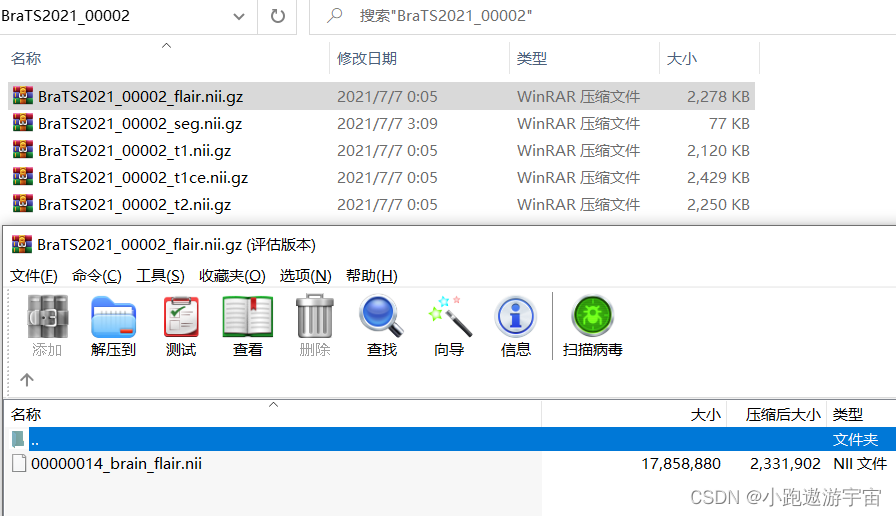

训练集其中一例MRI扫描(包含4个模态的3D图像以及1个共享标签)

1、在训练集中包含1251例核磁共振成像扫描,每例扫描包含4种模态的3D图像以及1个共享标签,其中4种模态分别是t1、t1ce、t2、flair: